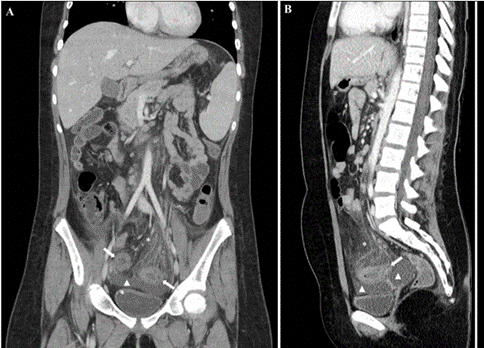

The pain subsided, but the patient presented fever of 38ºC, diarrhea and pruritic macular rash of the trunk. On day 2 of admission, she presented sudden clinical worsening with lethargy, fever, tachycardia (150 beats per minute) with blood pressure at the lower limit of normal (systolic blood pressure 107 mm Hg/diastolic blood pressure 54 mm Hg), oliguria and mild metabolic acidosis. Given the suspicion of MIS-C with shock associated with COVID-19, she was admitted to the PICU. Electrocardiogram and echocardiography were normal. Laboratory results are summarized in (Table 1). Other etiology was ruled out with a full serology and body fluid cultures. The patient received vasopressor support (noradrenaline 0.1 mcg/kg/min), antibiotics for suspected abdominal bacterial co-infection (ceftriaxone 50 mg/kg/24h and metronidazole 10 mg/kg/8h), COVID-19 treatment (hydroxychloroquine 6.5 mg/kg/12h 4 doses; low-molecular-weight heparin 0.5 mg/kg/12h; vitamin K 10 mg/dose), and MIS-C treatment (interleukin-6 inhibitor (tocilizumab) 8 mg/kg/24h 1 dose; intravenous immune globulin 2 g/kg/24h 1 dose; methylprednisolone 2 mg/kg/24h 1 dose). The study was completed with abdominal computed tomography (CT) (Figures 1B, 2A & 2B). We observed radiologic signs of severe acute sigmoiditis, homogeneous splenomegaly of 140 mm and mild bilateral pleural effusion with passive atelectasis of lung parenchyma but no parenchymatous involvement characteristic of COVID-19 in the lower thorax included in the CT.

Figure 2: A) Abdominal contrast-enhanced CT (portal venous phase), coronal image. B) Abdominal contrast-enhanced CT (portal venous phase), sagittal image. Segmental concentric wall thickening of the sigmoid colon, with marked proximal involvement (white arrows). Pericolonic fat stranding and comb sign (engorgement of the vasa recta), as signs of inflammatory changes (asterisk). Pelvic free fluid (triangle).

In our case, US revealed hyperechoic pelvic mesenteric fat related to inflammatory changes and concentric wall thickening of the sigmoid colon (Figure 1A). However, acute appendicitis could not be ruled out because the cecal appendix was not visible. CT performed after clinical worsening revealed marked concentric parietal thickening of sigmoid colon suggesting acute inflammatory-infectious sigmoiditis, increased density and trabeculation of adjacent and retroperitoneal fat, engorgement of the vasa recta (comb sign), lymph node swelling and a moderate amount of intra-abdominal fluid in relation to marked inflammatory changes; ileocecal appendix was normal (Figures 1B, 2A & 2B).